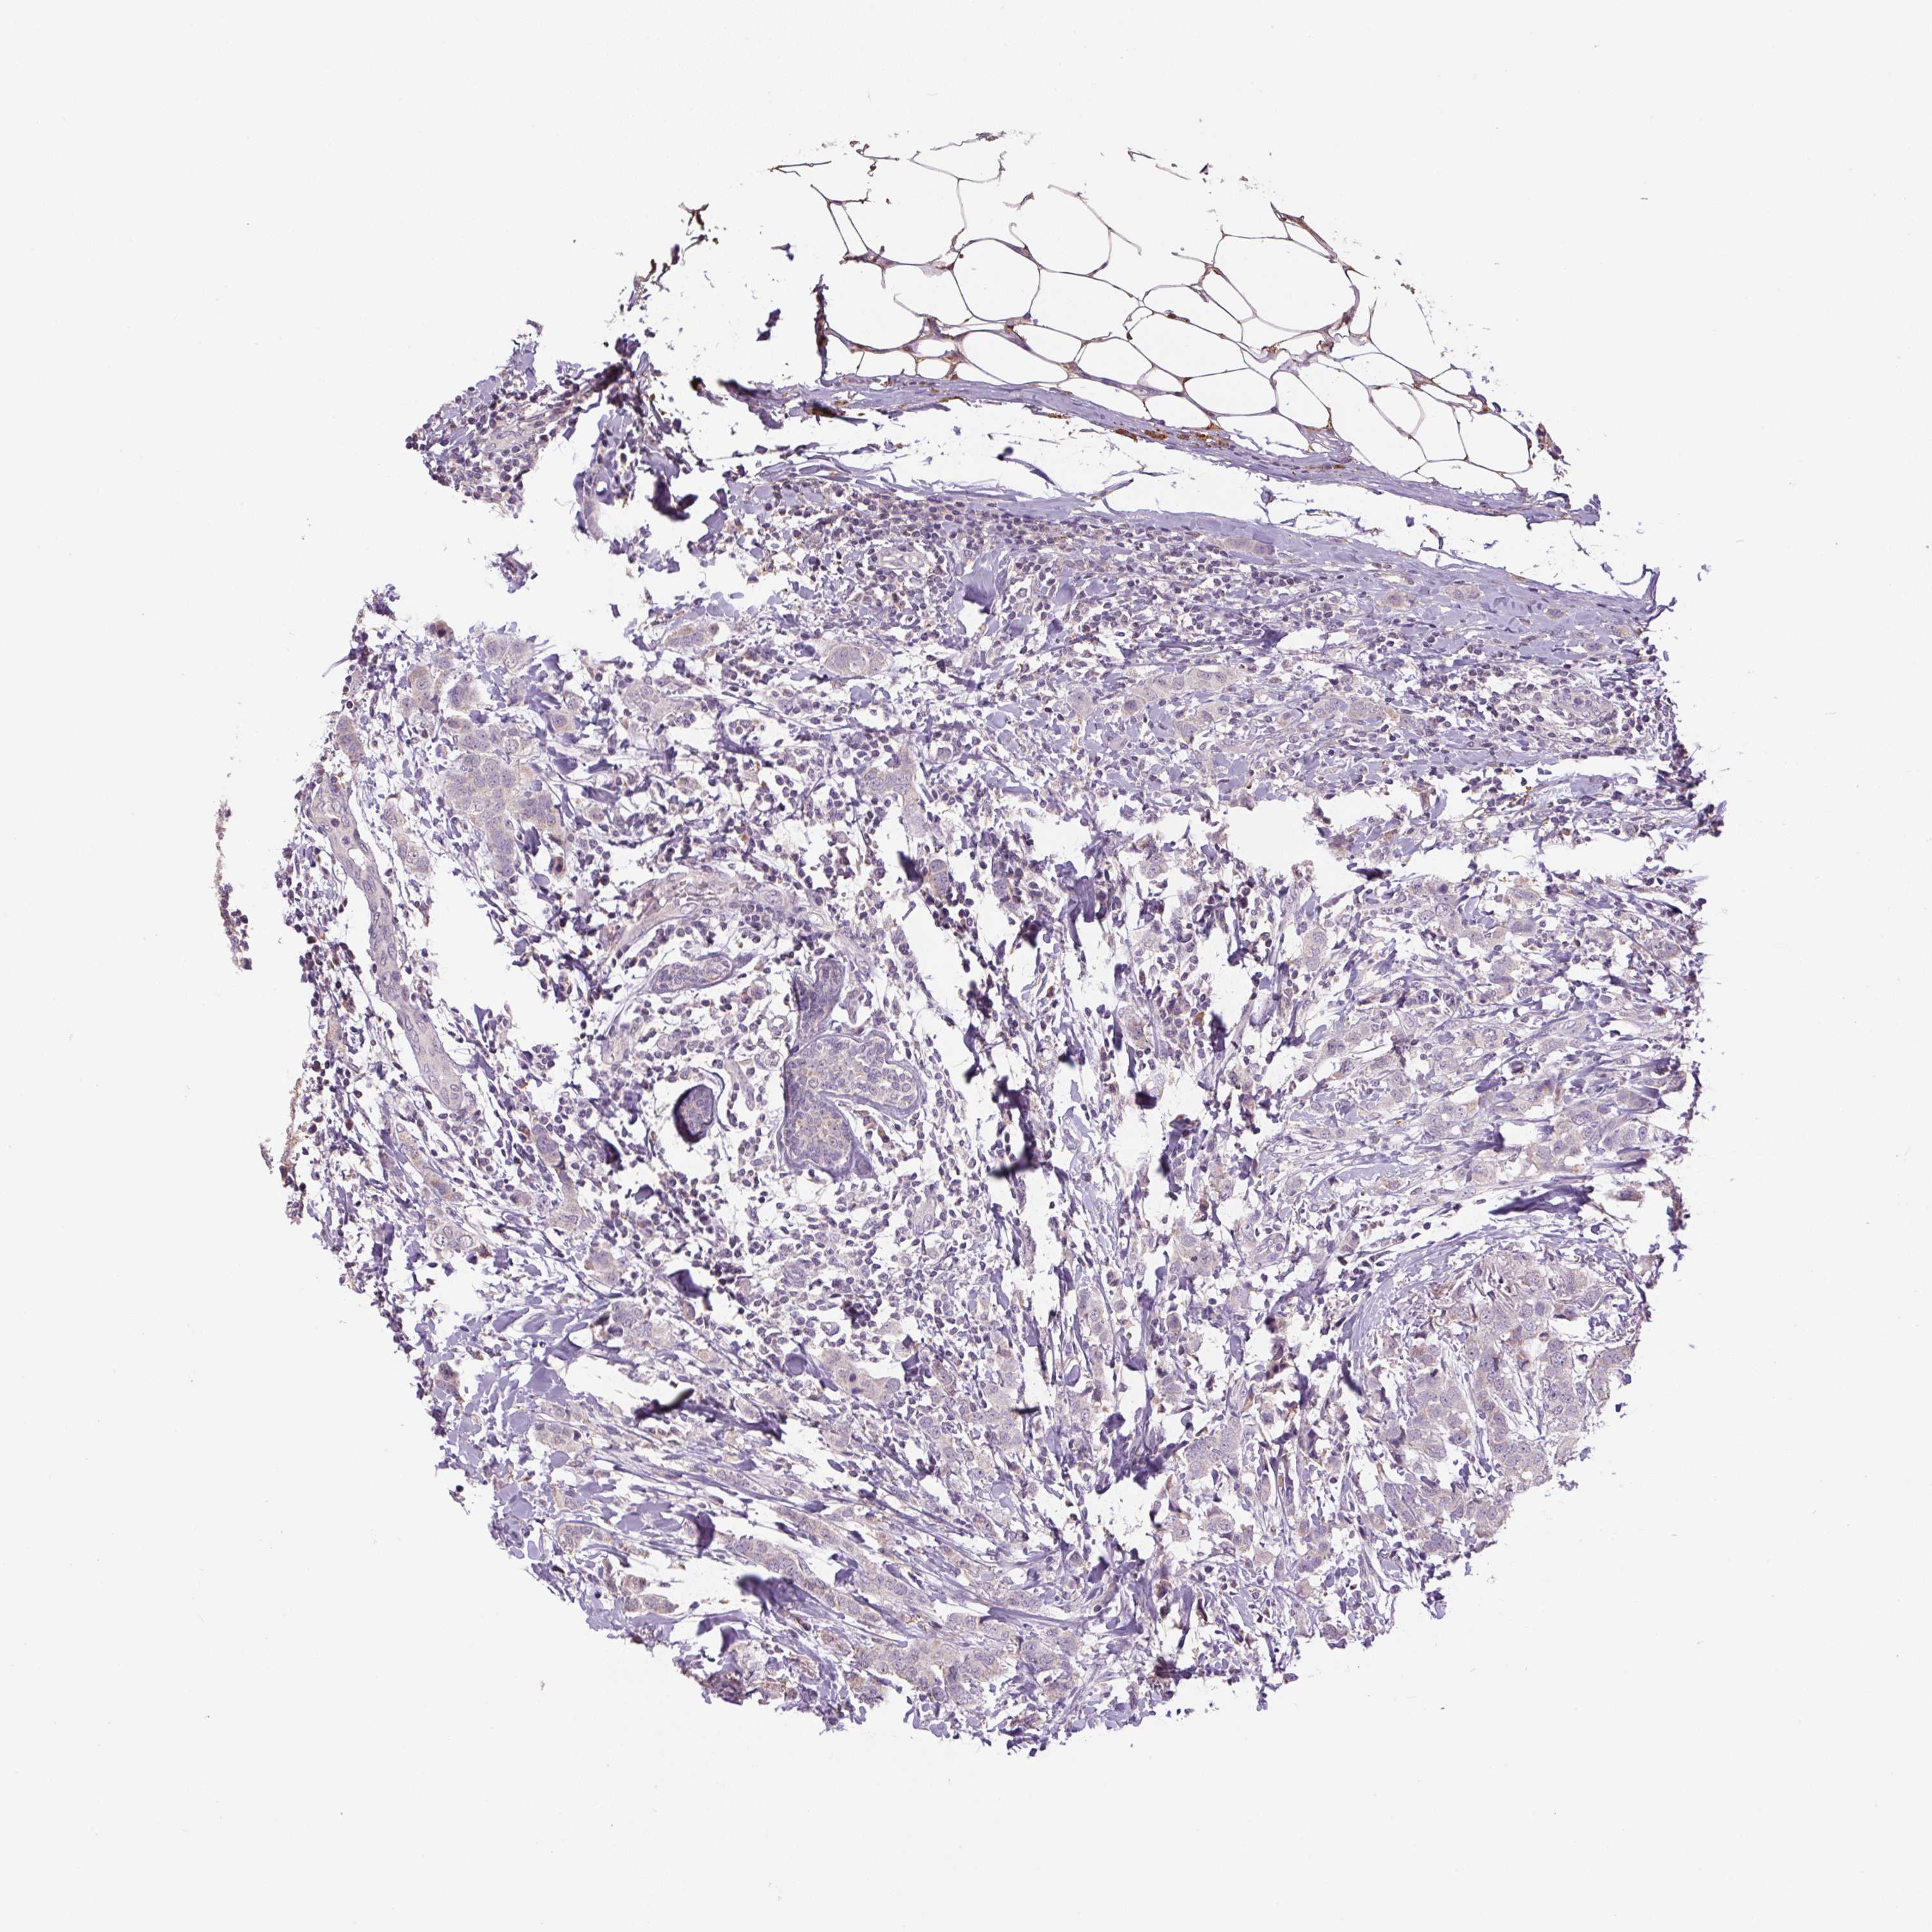

CANCER BREAST CANCER Show tissue menu

BRCA TCGA BRCA VALIDATION PROTEIN EXPRESSION